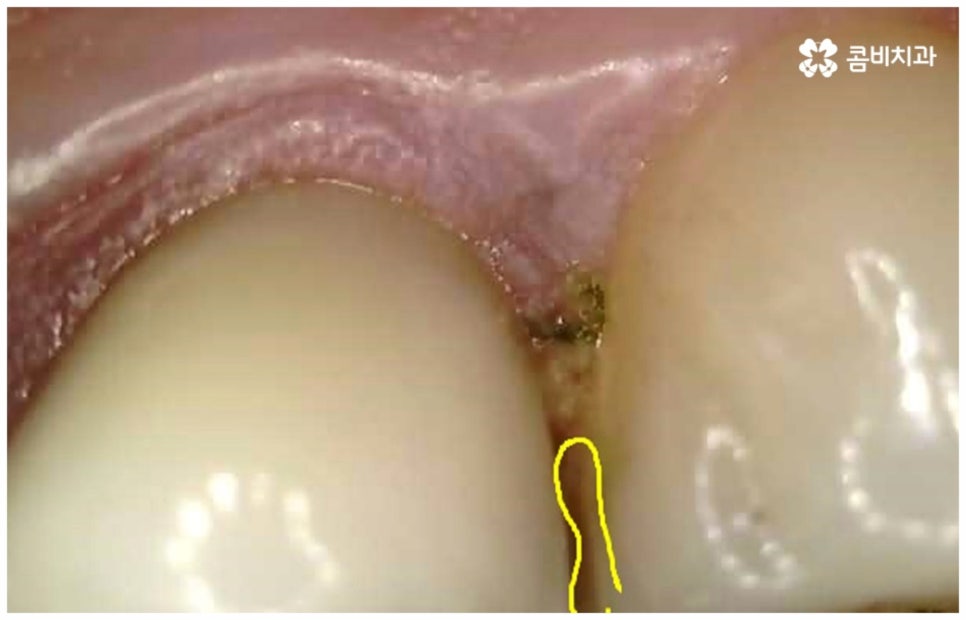

어금니는 위치상 구강 내 가장 안쪽에 위치하므로 평상시 양치질을 잘 해 준다고 해도 음식물 찌꺼기가 남아있을 가능성이 커 충치 발생률이 높은 치아라고 할 수 있는데요. 이렇게 충치로 인한 손상 때문이 아닌 다른 이유로 어금니신경치료 를 진행해야 하는 경우도 있을 수 있어요. 예를 들어 20살 전후로 사랑니가 나오면서 삐뚤어지거나 일부가 매복된 채로 비정상적인 맹출을 하게 되면 앞의 어금니 뿌리에 압박을 주는 등 좋지 않은 영향을 줄 수 있는데요. 이 때 바로 사랑니를 발치하지 않고 그대로 방치한 채 시간이 오래 흘러 어금니까지 손상이 생겼을 경우 어금니신경치료 를 받아야 할 수 있어요. 그밖에도 외부에서 큰 충격을 받아 어금니가 깨지거나 부러져서 드물게 신경이 노출된 경우에도 감염된 신경 제거가 필요할 수 있는데요.